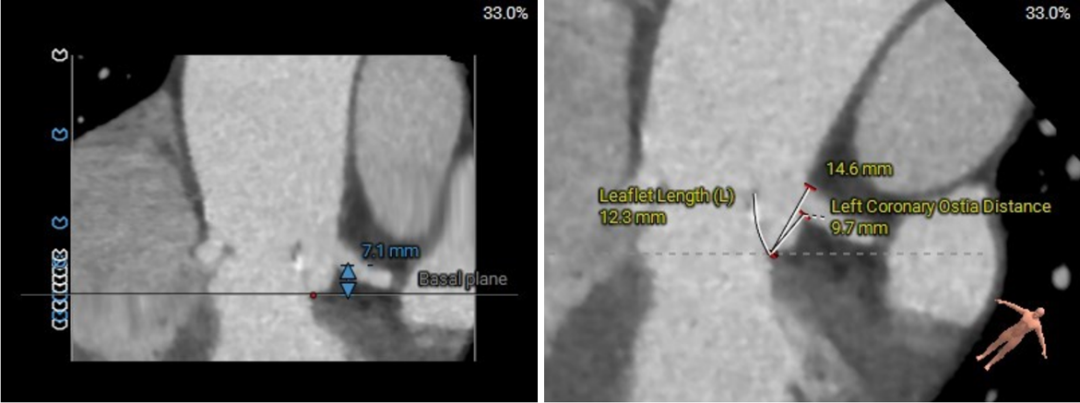

冠脉高度、瓣叶长度及左室内径

左冠高度:7.1mm;右冠高度:13.4mm;

左冠-窦底距:9.7mm;右冠-窦底距:14.4mm;

左冠瓣长度:12.3mm;右冠瓣长度:14.8mm;

左冠水平高度较低,开口内径较大,瓣叶略长,LCC至对合缘距离约30mm,存在一定左冠阻塞风险。

左室室间隔基底部肌性凸起,增加了流出道锚定有利因素。